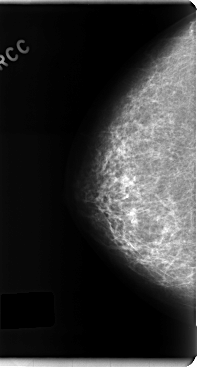

C_0215_1.RIGHT_CC

RIGHT_CC LINES 4784 PIXELS_PER_LINE 2552 BITS_PER_PIXEL 12 RESOLUTION 50 NON_OVERLAY